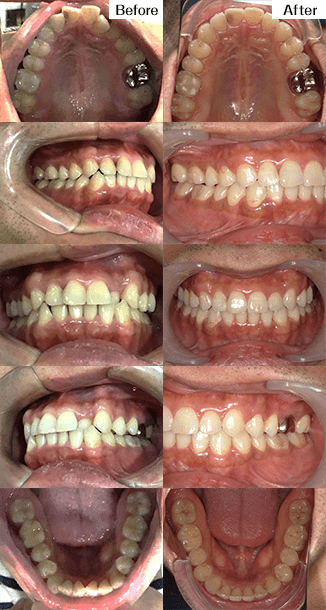

治療方法 マウスピース型矯正装置

(インビザライン)治療の説明 主訴:出っ歯、開咬 年齢 20才 抜歯箇所 非抜歯 ![]()

治療費用 767,800円

(相談・検査・診断料 無料、調整料 無料)治療期間 1年2ヶ月目 通院回数 10回 治療の内容・詳細 カスタムメイドで制作されたマウスピースを定期的に交換しながら少しずつ歯に適切な力をかけて歯並びを整えていく矯正治療です。 治療の副作用(リスク) 装着時間が少ないと治療期間が長引く可能性があります。

他の矯正治療法と同様に、疼痛・歯根吸収・歯肉退縮の可能性や適切な保定をしないと治療後に後戻りすることがあります。